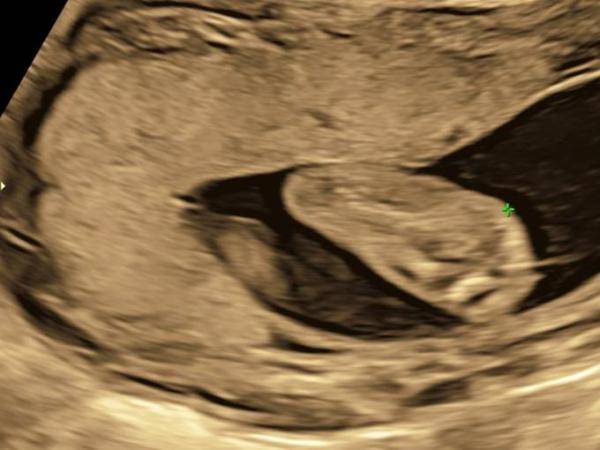

Hallo. Also ich würde auch sagen Mädchen. Bei meinen Söhnen sah das ganz anders aus (siehe Bild) Liebe Grüße Julia

Bild zu